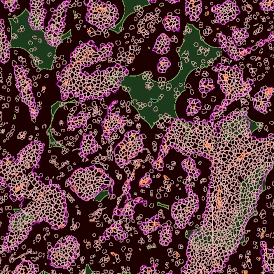

Application Note

14 Feb, 2023

Case Study: Analysis of FISH Using Tissue Cytometry

The IF Dots App in StrataQuest streamlines automated analysis of FISH stainings by detecting nuclei and quantifying dots per cell. This case study shows how the workflow enables accurate, exportable data for genetics research and clinical applications.